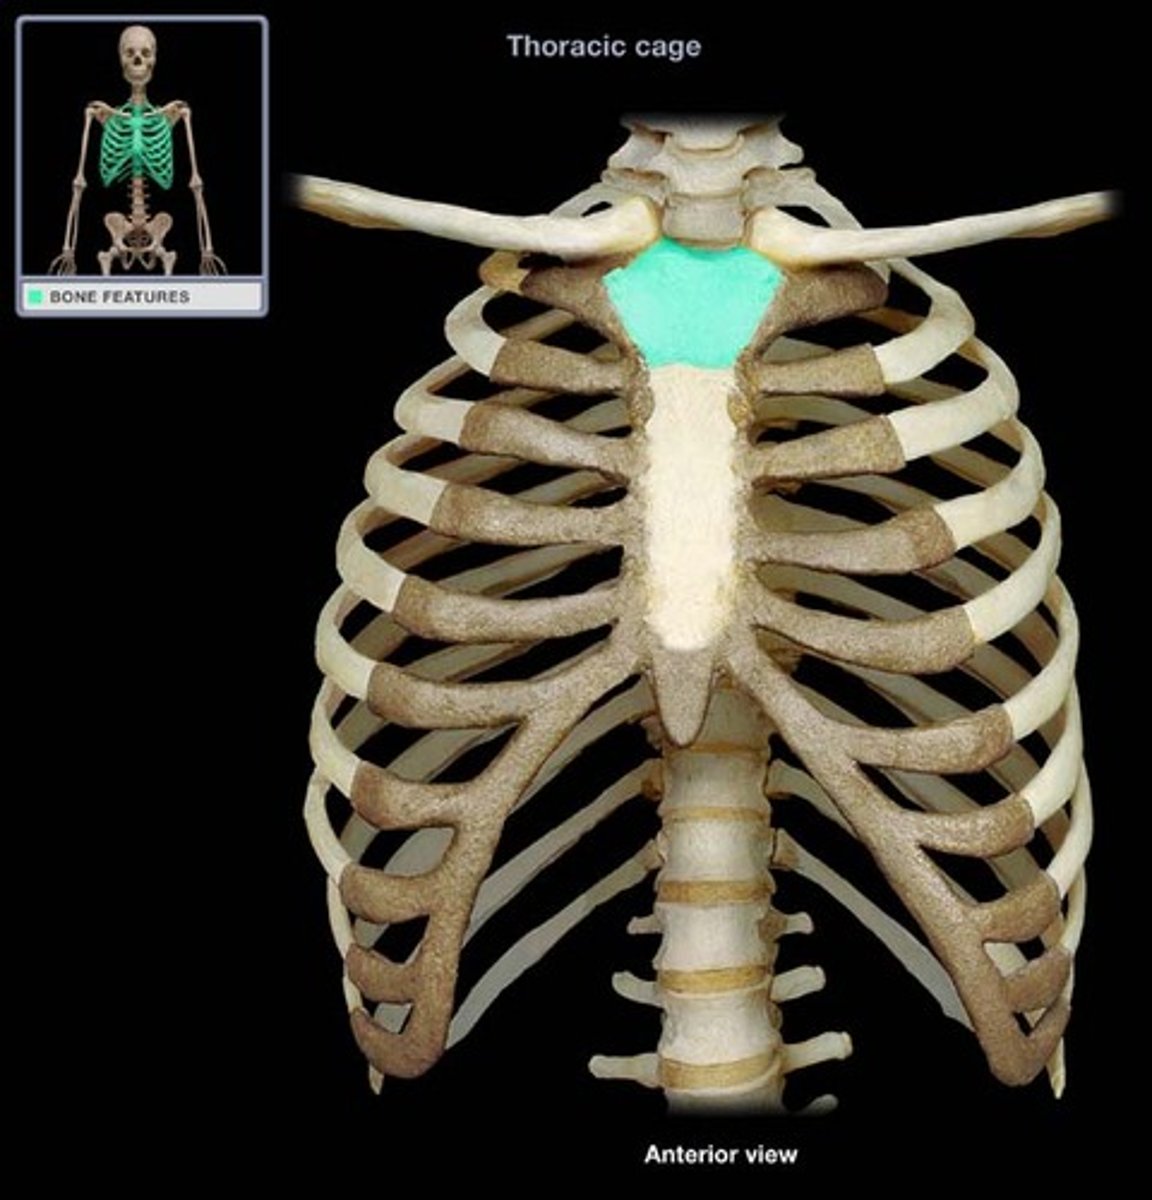

manubrium

What is this structure?

sternal angle

What is this structure?

clavicular notch

What is this structure?